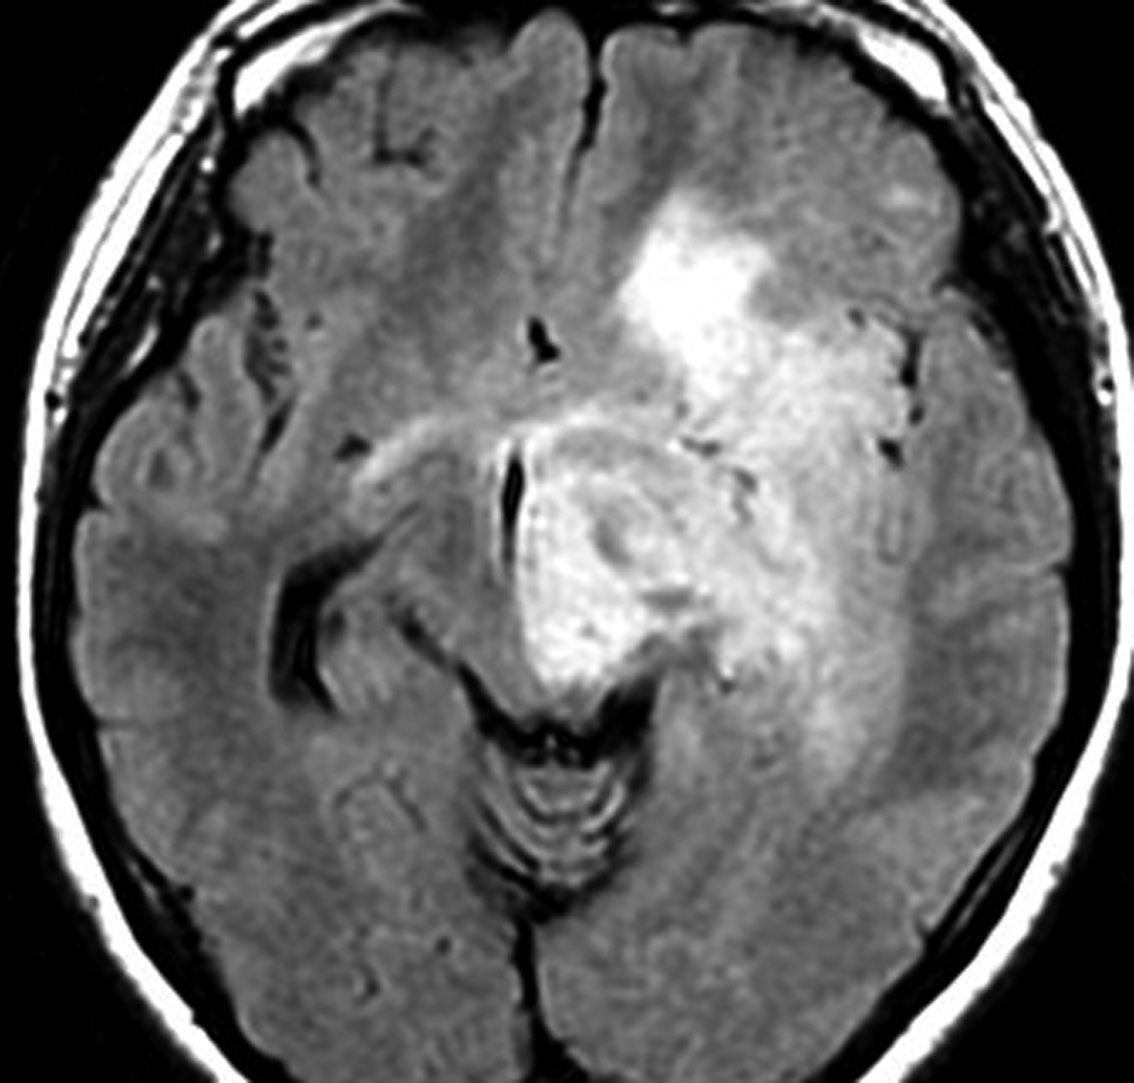

軽度の左下肢の麻痺で発症した50代の患者さんです。一見,かつてのグリオマトーシス gliomatosis あるいは diffuse hemispheric glioma WHO grade 4 のように見える非常に広範囲な病変です。しかし,病理診断は 星細胞腫 IDH mutant WHO grade 2でした。

放射線治療によく反応し,片麻痺は消失して,画像上の腫瘍高信号もほぼ消失しています。